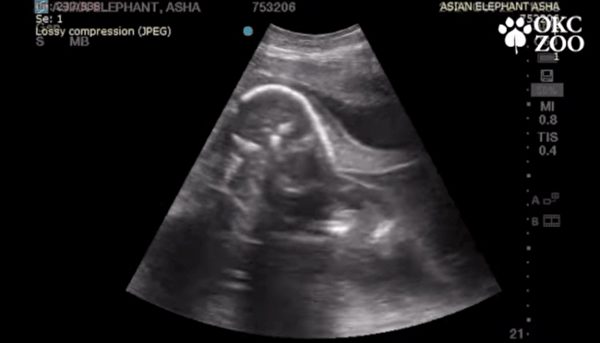

美国奥克拉荷马州的奥克拉荷马市立动物园(Oklahoma City Zoo)最近分享了一只小象在妈妈腹中的超音波扫描图,让人们觉得很可爱。

该动物园在去年11月分享的一段短片中表示,园内一只名叫阿莎(Asha)的25岁亚洲象正怀孕在身,预计在2022年2月生产,这将是它的第4个孩子。

大象的怀孕期长达22个月,而当时阿莎已经怀孕8个月。尽管怀孕期还没过一半,但小象的雏形已经在阿莎的肚子里形成。

从兽医所做的超音波扫描图可以清楚地看到,这只小象已经有了头部、腿部和象鼻,而它与阿莎的健康情况都很好。